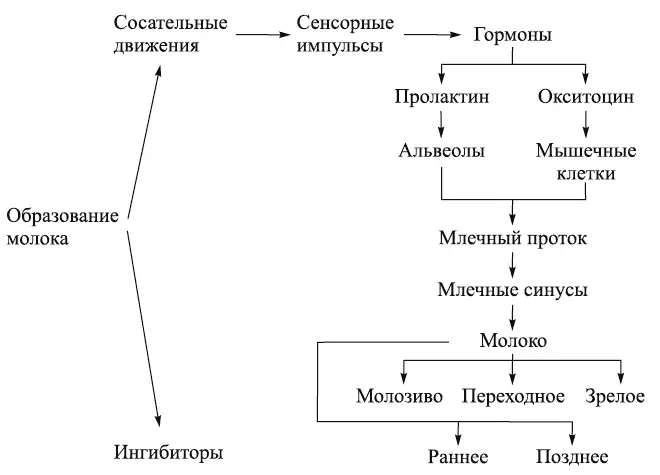

Схема 1. Образование грудного молока